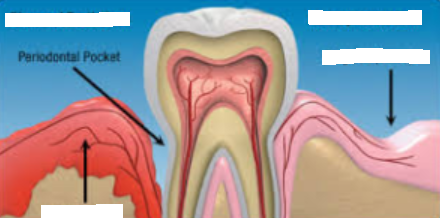

infrabony pockets

occurs when vertical bone loss is present

classified into infra-bony defects or osseous defects

JE is located apical to the crest of the alveolar bone

suprabony pockets

occurs when horizontal bone loss is present

base of the periodontal pocket is coronal to the alveolar crest

JE is located coronal to the crest of the alveolar bone

gingival pocket (pseudo-pockets)

deepening of the gingival sulcus as a result of swelling or enlargement of the gingival tissue

caused by: detachment of the coronal portion of JE and/or increased tissue size due to swelling

periodontal pocket

pathologic deepening of the gingival sulcus

results from either apical migration of the JE, destruction of the periodontal ligament fibers, or destruction of the alveolar bone

pseudo-pocket

no apical migration of the JE, coronal portion of the JE detaches from the tooth that results in increase probing depth